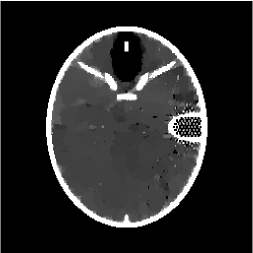

Figures 4 and 5 present visual reconstruction results of the SL phantom and the FB phantom, respectively, both under high additive Gaussian noise (). In particular, Figure 4 is to recover the SL phantom using 7 radial lines. The model has severe streaking artifacts due to this extremely small number of data obtained on the radial lines. The minimization on the gradient yields significant improvements over the baseline model (TV). The proposed algorithm outperforms the previous ADMM approach at the outer ring and boundaries of the three middle oval shapes, which are more obvious in the difference map to the ground truth. On the other hand, the FB phantom has finer structures and lower image contrast compared to the SL phantom. As a result, it requires 13 radial lines for a reasonable reconstruction. As we observe in Figure 5, the overall geometric shapes are preserved. At the same time, many speckle artifacts appear in the reconstructed images by no matter which algorithm is used.